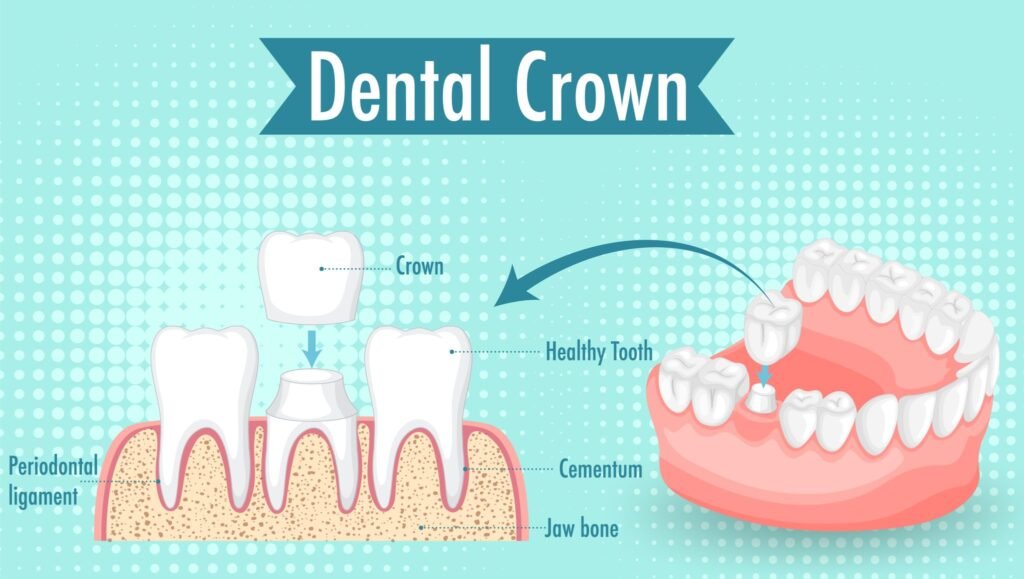

What is a Dental Crown

A dental crown is a tooth-shaped covering that is placed over a damaged tooth. The crown restores the shape and size of the tooth, increases its strength and also the way it looks. A well-made crown is indistinguishable from other teeth both in appearance and strength.